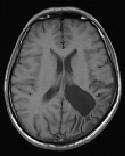

Figure 1: Brain tumour MRI: Magnetic resonance imaging (MRI) of the brain is a safe and painless test that uses a magnetic field and radio waves to produce detailed images of the brain and the brain stem. An MRI scanner consists of a large doughnut-shaped magnet that often has a tunnel in the center. Patients are placed on a table that slides into the tunnel. During the exam, radio waves manipulate the magnetic position of the atoms of the body, which are picked up by a powerful antenna and sent to a computer. The computer performs millions of calculations, resulting in clear, cross-sectional black and white images of the body. These images can be converted into three-dimensional (3-D) pictures of the scanned area. This helps pinpoint problems in the brain and the brain stem when the scan focuses on those areas [3].